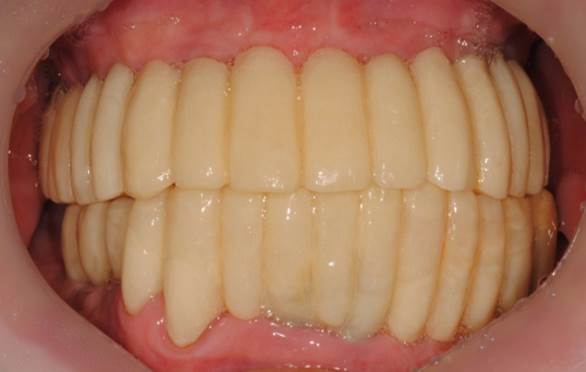

Clinical case: Advantage of fuse abutment with AnyRidge implant for immediate loading in

upper fully edentulous case

- Courtesy of Dr. Kwang Bum Park -

Keywords

AnyRidge, fuse abutment, immediate loading, maxillary fully edentulous case, initial stability, zirconia customized abutments, PMMA temporary bridge, CAD/CAM technique, edentulous, Dr. Kwang Bum Park

Products:

AnyRidge implant system, fuse abutment

“AnyRidge shows excellent esthetic results

with Zirconia prosthesis in full-mouth rehabilitation case . ”